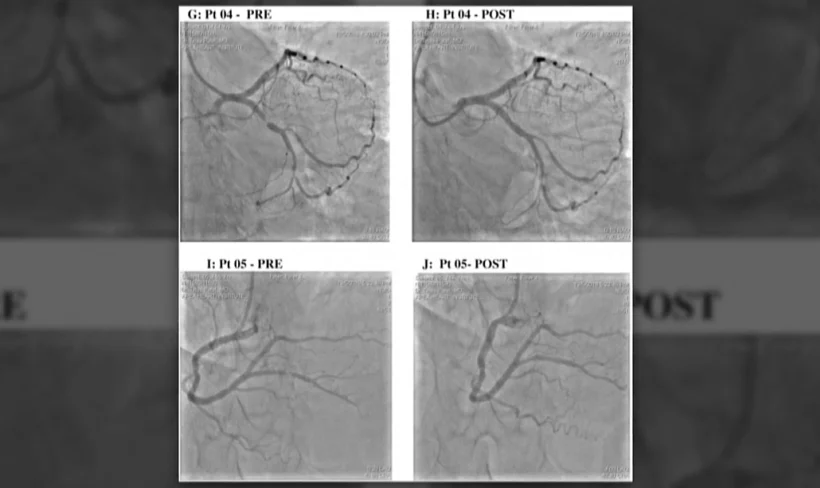

רופא בהודו ביצע סדרה של חמישה הליכים כירורגיים בלבם של מטופלים כשהוא במרחק של 32 קילומטרים מהם. ההליכים הרפואיים, שהוגדרו מוצלחים, היו בעיקר התערבות כלילית וחידוש זרימת דם בעורק חסום ובוצעו באמצעות רובוט שנשלט מרחוק. המקרה פורסם בכתב העת "EClinicalMedicine" של המגזין הרפואי "דה-לנסט".